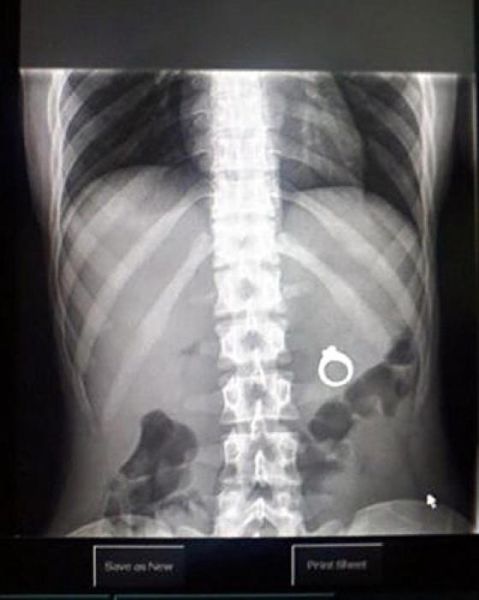

These x-rays will make you wonder how this could ever have happened in the first place.